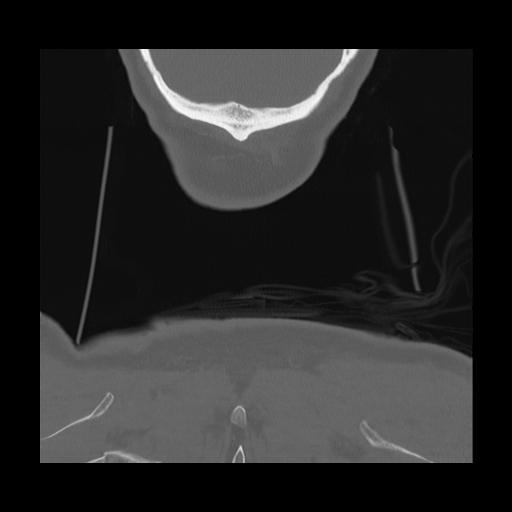

16 HUESO,,Coronal,2.000,HUESO,Coronal,